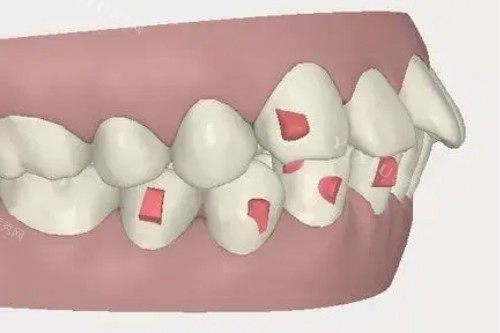

牙齿矫正项目

隐形矫正采用透明的牙套,美观舒适且可自行摘戴。不同品牌的隐形矫正器在材料、设计和技术上有所不同,价格也会有较大差异。

传统金属托槽矫正:5200 元起

传统金属托槽矫正价格相对较低,是一种较为经济实惠的矫正方式。不过,它的美观度相对较差。